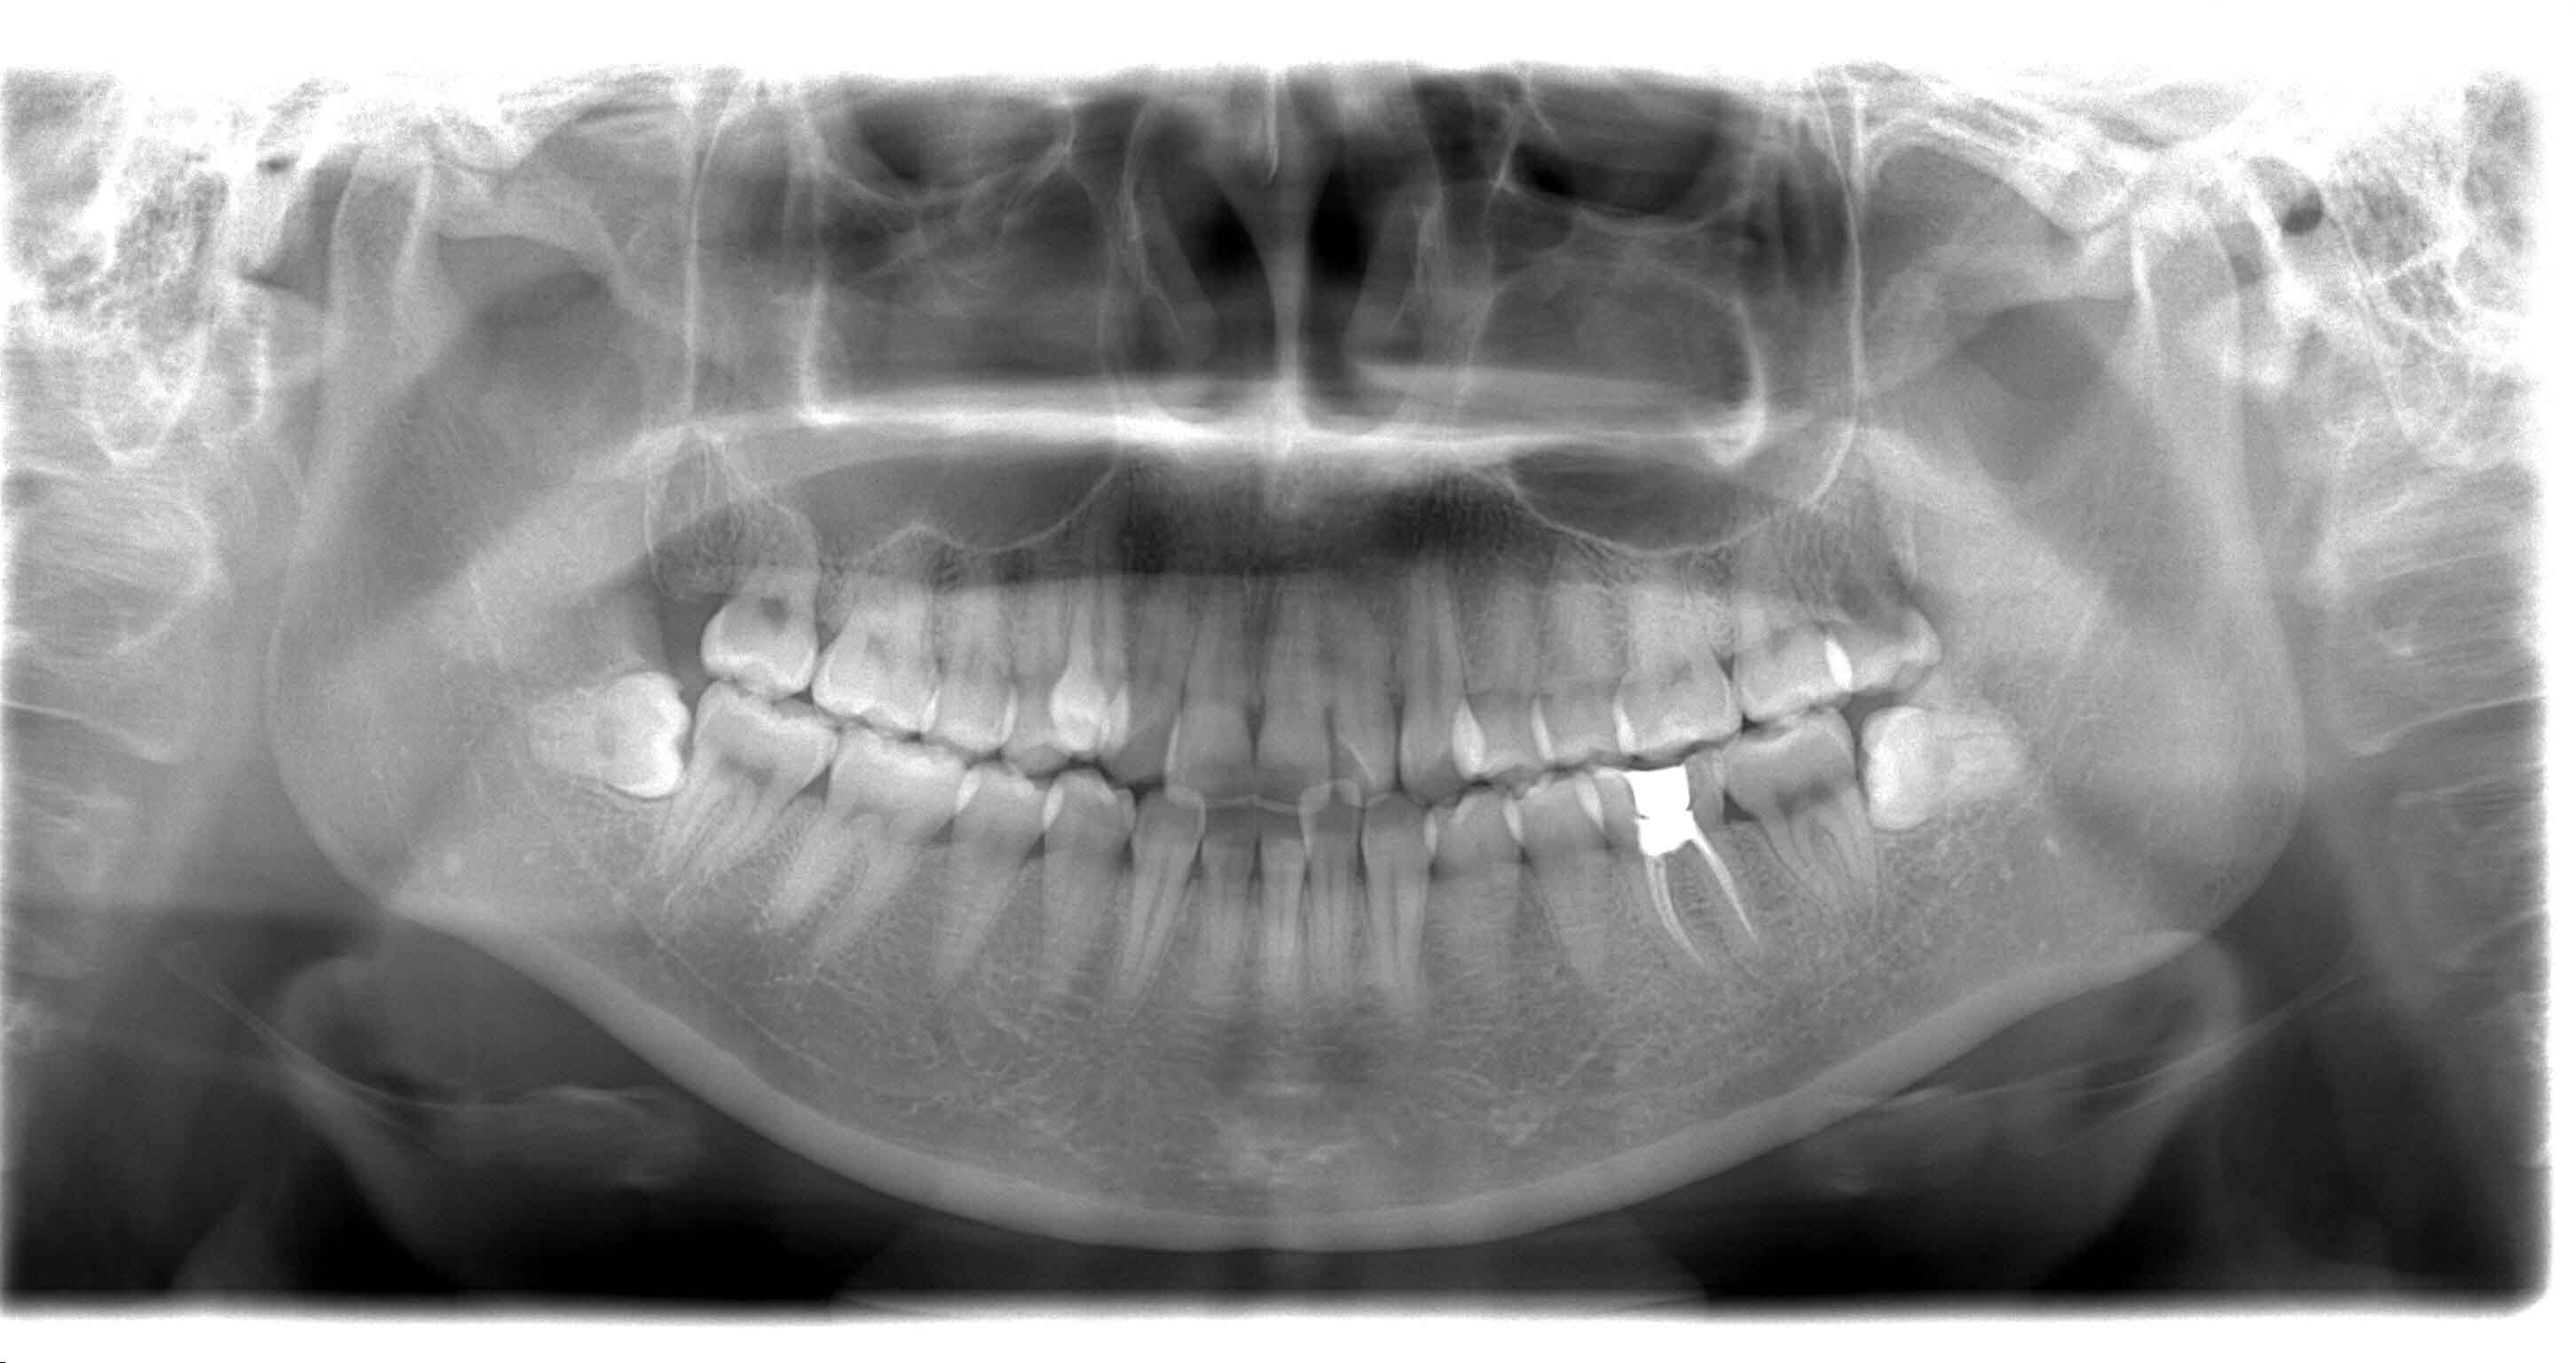

很多人牙一疼,就想着去医院把牙拔了一了百了,但其实牙齿该不该拔,还得分情况而言。

牙齿疼痛可能是有多种因素引起的,比如 龋齿、牙龈炎、牙周炎 等,很多情况下患牙都是有机会被“拯救”的。

哪些情况下牙齿可以保留?哪些情况下牙齿需要拔除?今天我们就来一起看看吧~

需要注意的是,每个人的情况都是不同的,因此在拔牙之前,最好先咨询牙医,了解所有可能的治疗选项,并权衡拔牙的利弊。